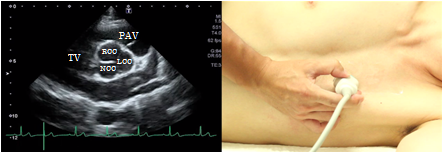

Aortic valve level

At the aortic valve level of the short axis view of the left ventricle, the 3-cusp structure consisting of right coronary cusp of the aortic valve, the left coronary cusp, and the non-coronary cusp can be confirmed. The pulmonary valve can be seen on the right side of the screen and the tricuspid valve is on the left side. This view is used to visualize the cusps of the aortic valve, to measure the aortic valve area. Furthermore, this view visualizes pulmonary valve, tricuspid valve, the origin of the coronary arteries and utilize it for the classification of ventricular septal defects.